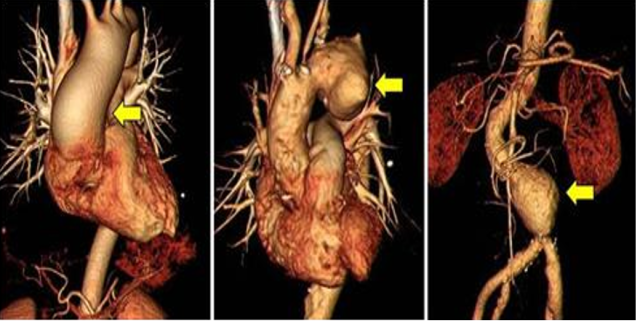

대동맥류(Aneurysm)는 대동맥을 이루는 3층 중 중막에 위치한 콜라겐이 노화로 약화돼 생기는 질환이다. 혈압을 견디지 못한 대동맥의 직경이 정상 혈관보다 1.5배 이상 늘어난다. 대동맥류는 고령이거나 오랫동안 고혈압을 앓았던 환자에서 주로 발생한다. 유전성 대동맥질환을 가진 경우 상대적으로 젊은 연령대에서도 발병할 수 있다. 대동맥류는 파열된 경우를 제외하고는 대부분 특별한 증상이 없다. 드물지만 대동맥궁에 발생한 대동맥류는 갑자기 쉰 목소리로 변하는 증상으로 발견되기도 한다.

대동맥이 늘어나다가 파열되는 경우는 치료를 하더라도 사망률이 굉장히 높다. 따라서 파열되기 전에 치료를 하는 것이 중요하다. 치료가 필요한 시점은 CT 촬영을 통해 측정한 대동맥의 크기가 5cm를 넘거나 대동맥류의 크기가 커지는 속도가 6개월 동안 0.5cm 이상 빠른지를 따져 결정한다. 대동맥류의 모양이 주머니형이거나 혹처럼 짧은 구간에서 튀어나왔는지 여부도 중요한 요인이다. 대동맥류가 발견됐더라도 크기가 5cm 이하라면 즉각 치료하는 대신 적극적인 혈압 조절, 금연, 운동 등 생활습관 개선이 권고된다. 정기적인 CT 검사도 필수적이다. 대동맥류는 수술 또는 대동맥 내 스텐트 삽입술로 치료한다. 수술은 대동맥의 모양, 위치와 관계 없이 모두 가능하다. 다만 대동맥에 스텐트를 삽입하려면 대동맥류 주위 정상적인 혈관의 범위를 포함해 대퇴동맥의 크기나 질환 유무, 유전성 대동맥질환의 유무 등을 확인해야 한다. 대동맥류의 위치에 따라 수술과 스텐스 삽입술을 함께 시행하는 하이브리드 수술도 가능하다.